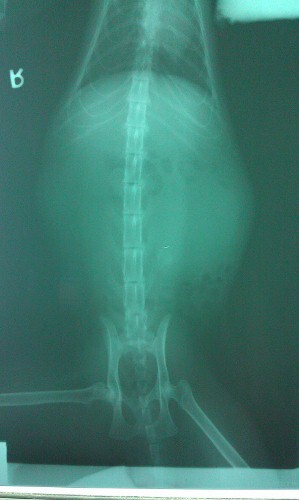

主題: 仁武腳疑似捕獸夾傷, 腎積尿90cc的大黑公貓 申請者姓名: 劉雅雲 花色: 申請日期: 2012-03-22 07:50:29 申請者部落格: 申請者臉書網址: 所在縣市/合作醫院: 高雄市/樂生動物醫院 治療費用: 5000元 需求人數: 5人 已結案 (2012-04-10 13:14:54) 報名人員: 喵卡(已付款)、鍾玉芬(已付款)、蘇佩玉(已付款)、Kate(已付款)、平野耕太(已付款)、 候補人員: 動物病情說明: 這是誘捕結紮的公貓, 因為他腳看起來好像有一點傷, 沒想到結紮麻醉醫生檢查發現傷口有點像捕獸夾傷, 結紮完暫時住院等腳傷好, 但幾天後發現不吃, 精神不濟. 驗血和X光檢驗, 一邊腎腫很大, 緊急抽尿90cc.

1. 血液生化驗血 1000

2. 血液電解質驗血 500

3. 住院3/8 - 3/12 (300x4=1200)

4. X光 (400x2=800)

5. 鎮定腎臟穿刺抽尿 1500

<貓咪因為需要摘除一個腎臟,已轉院到回生進行手術>動物近況說明: 目前已在回生做完手術 也出院了, 暫時放在朋友家在觀察休養後才會放回原地